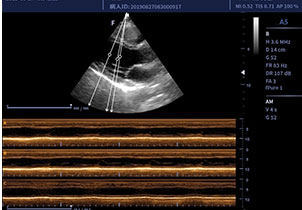

• P5-2/P4-1相控阵探头

适用于心脏、小儿科等

临床超声检查